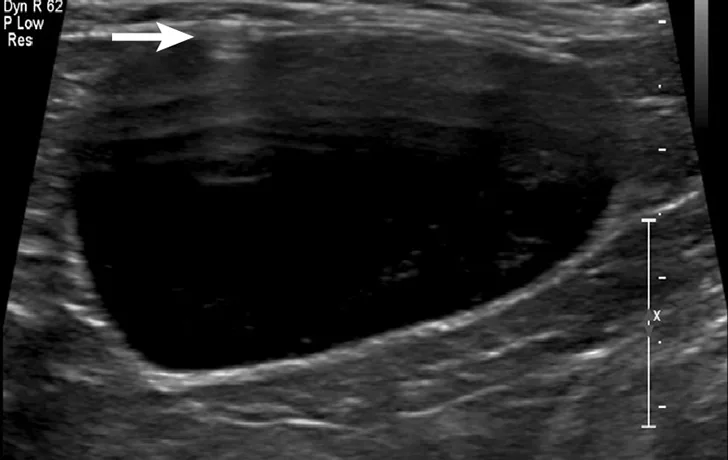

Cystocentesis is often performed with ultrasonographic guidance, although this is not required (ie, blind cystocentesis). Using ultrasonography can help direct visualization of the needle in the urinary bladder lumen, avoiding iatrogenic damage of surrounding structures (Figure 1). The relative size of the bladder, echogenicity of its contents, and any obvious structural abnormalities can also be observed. A primary advantage of blind cystocentesis is that it does not require special equipment. Cystocentesis can be challenging to perform in patients that have abdominal effusion and should be performed with ultrasonographic guidance in such cases.

Ultrasonographic image showing the cranial aspect of the urinary bladder (A), identified just before ultrasound-guided cystocentesis. It is important to adjust the depth of the image so that the urinary bladder is focused and to consider the depth of the urinary bladder using a machine scale that should be present on the ultrasound screen; in smaller patients the needle may only be partially inserted and not reach the hub (B; arrow).